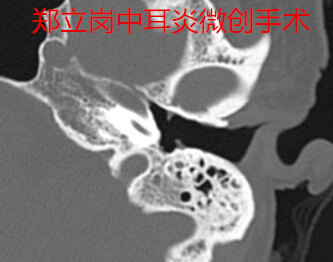

患者*党**,女,57岁,河南平顶山鲁山人。患者于1年余前无明显诱因出现左耳溢液,间断性,脓液为淡黄色、无血丝、量不多、不臭,伴左耳听力下降,逐渐减退,无明显耳痛,偶伴嗡嗡样耳鸣,伴左耳闷塞感,无伴眩晕、恶心、呕吐等症状,予以药物治疗后症状可改善,但每遇感冒、耳道进水后易再次流脓。近1月来左耳未再流脓,今门诊以"左侧慢性化脓性中耳炎"收住入院,拟进一步手术治疗。患者左侧中等大小鼓膜穿孔,手术难度不大,这次做的是全麻耳内镜中耳炎微创手术。插管全麻后就开始了手术,在耳内镜下不用做任何的体表切口,直接翻起外耳道鼓膜皮瓣。翻起皮瓣的过程中出血比较多,翻起皮瓣后取合适大小的耳屏软骨修剪后修补鼓膜,鼓膜修补好后检查了两遍确认没问题后就结束了手术。整个的手术用时约60分钟,由于出血做的非常的艰苦,但还算比较顺利。术后查房患者无明显的不适,无手术相关的并发症。